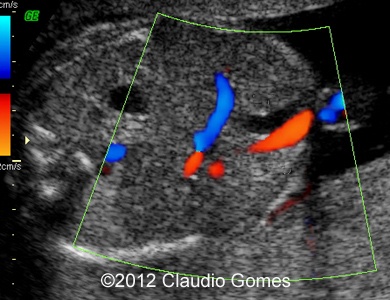

Images 6, 7: 37 weeks, four-chamber and five-chamber view with the aorta and Azygos vein

f3

Fig7

Images 8-11: Persistent right umbilical vein and Inferior vena cava interruption with continuity of the flow via Azygos vein on grayscale and color Doppler